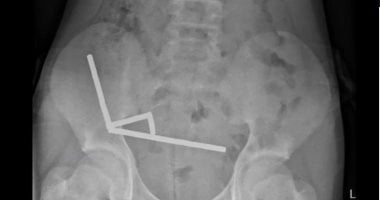

نجح فريق جراحي في إزالة نحو 100 مغناطيس نيوديميوم عالي القوة من أمعاء مراهق يبلغ 13 عامًا في نيوزيلندا كان قد اشتراها عبر الإنترنت.

أوضحت المستشفى أن المغناطيسات، مقاسة 5×2 ملم، بلغت أعدادها بين 80 و100 مغناطيس، وتم جلب بعضها من منصة تيمو عبر الإنترنت قبل نحو أسبوع من إجراء العملية.

وأظهرت الأشعة أن المغناطيسات تكدست في أربعة خطوط مستقيمة داخل أمعاء الطفل، وبدا أنها في أجزاء منفصلة من الأمعاء ملتصقة ببعضها بفعل القوى المغناطيسية.

قال الأطباء إن ضغط المغناطيسات تسبب في نخر في أربع مناطق من الأمعاء الدقيقة والأعور، ثم أجرى الجراحون عملية لإزالة الأنسجة الميتة واستعادة المغناطيسات، وتمكن الطفل من العودة إلى المنزل بعد ثمانية أيام في المستشفى.